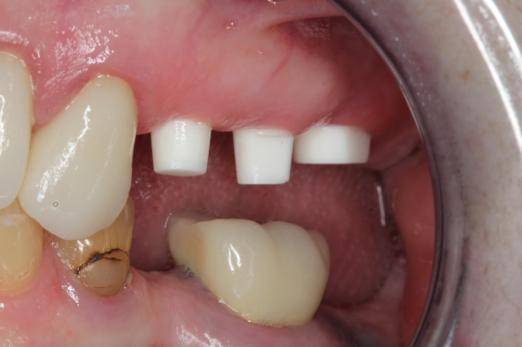

Occasionally dentists are presented with extreme challenges with long-term restorations and replacing missing teeth. Dentists must evaluate the patient's condition, develop optimum long-term oral health, and attempt to meet the patient's expectations. Figure 18 showed a class III malocclusion with deep bite, multiple abfractions, and less-than-ideal occlusal plane, but the patient wanted to replace his maxillary right canine only. A discussion with the patient regarding occlusal disharmonies and comprehensive recommendations for full-mouth rehabilitation revealed that the patient had a limited budget for dental care. The patient understood the ramifications of his comprehensive dental needs not being affordable. Decisions were made to atraumatically remove the maxillary right canine (Figure 19) and immediately place a ceramic dental implant (Figure 20). Polytetrafluoroethylene (PTFE) 4-0 sutures were placed to help support soft tissues, and then a full-arch Essix-style retainer with a flowable composite facial veneer was used to provide some esthetics during the patient's healing phase (Figure 21). The implant and the retainer were not to be in contactthe retainer may occlude with the opposing dentition and also be passive in relation to the ceramic implant.

Fig 18. Preoperative image.

Figure 18

Fig 19. Atraumatic extraction.

Figure 19

Fig 20. Immediately after extraction and placement.

Figure 20